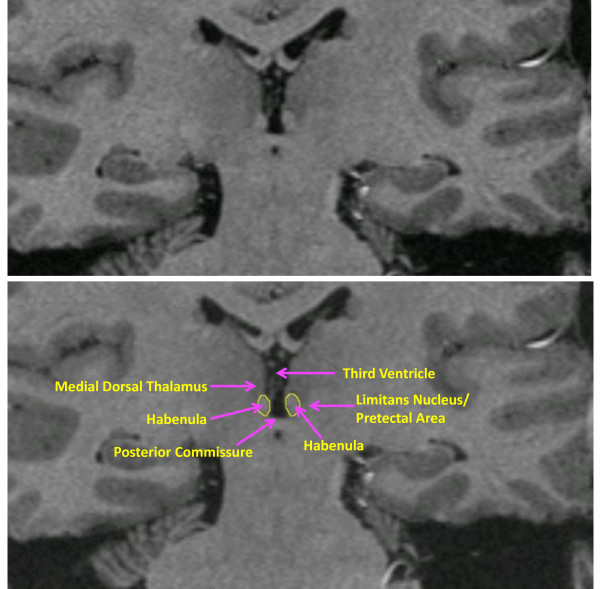

Findings: High-resolution images (resolution of approximately 0.4 mm3) were acquired using a 3T scanner and a pulse sequence optimized for tissue contrast resolution. The habenula was manually segmented by one rater blind to diagnosis. PTSD and HC participants did not differ significantly in absolute or normalized habenula volume. Post hoc analyses controlling for the effects of comorbid major depressive disorder (MDD) and type and age of trauma exposure were not significant. Further, there was no association between PTSD severity and habenula volume.